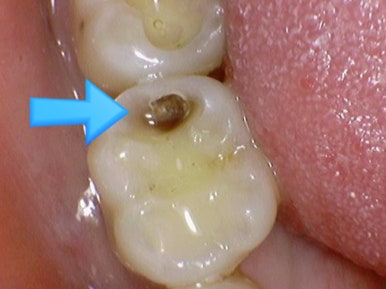

충치가 있다고 진단받았으나 겉에서 보이지 않는다고 방치하여

깨져서 온 사례

위 엑스레이 사진은 처음 방문하였을 때 엑스레이 사진입니다.

충치가 매우 심해 신경치료 해야 한다고 설명하였으나

환자분은 치아사진을 보면 치아가 썩은 것처럼 보이지 않는다면서(화살표 부분)

방치하다가 6개월이 지난 후 치아가 깨져서 오게 되었습니다.

이미 엑스레이 사진에서 충치가 매우 심함을 알 수 있고

치아 겉부분은 아주 얇게 남아있고 안은 무른 충치로 가득 차있음을 예상할 수 있습니다.